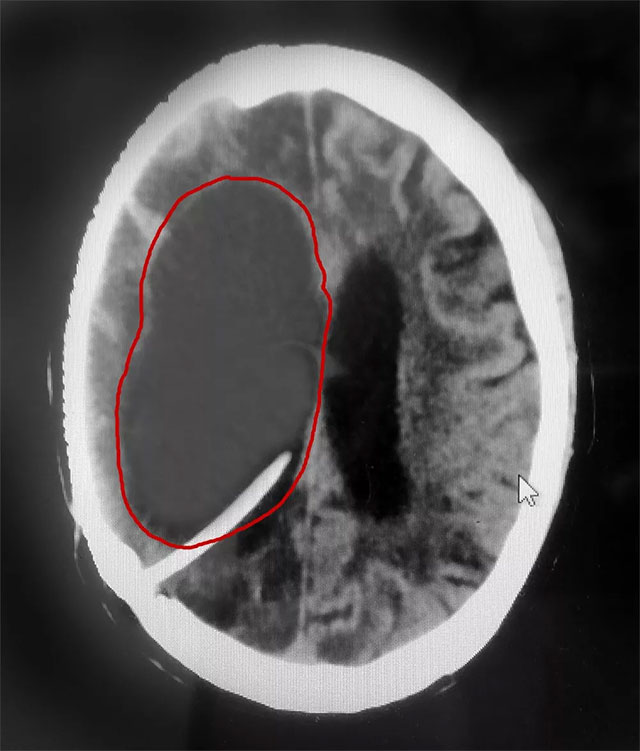

▲ 患者右侧脑室重度脑积水被及时置管分流

近日,上海蓝十字脑科医院神经外科6A病区收治了一位重度脑积水患者。三年前,患者金某(化名)因右侧大脑中动脉瘤破裂昏迷,在外院进行了开颅动脉瘤夹闭术和颅内血肿清除术。术后,由于伤口感染等原因,出现了脑脓肿、脑积水等并发症,长期处于昏迷状态。

在完善相关检查后,患者重度脑积水明确,若不及时治疗可能危及生命。

侯增欣主任介绍,脑积水形成之后,脑室系统由于脑脊液的积蓄而扩张。脑室进一步扩大,压力增高,导致脑脊液渗入脑室周围组织而引起白质水肿,若脑积水进一步发展,大脑皮层受压变薄,则可继发脑萎缩,导致智能障碍,轻者记忆力及计算力减退,常伴有迟钝、淡漠、缄默等。重者可呈痴呆。